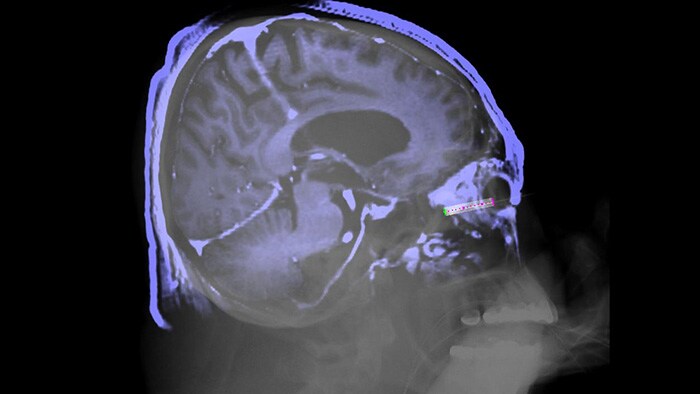

XperGuide ofrece una guía para la aguja con imágenes en 3D en directo, lo que le permite llevar los procedimientos con agujas percutáneas al quirófano híbrido. Superpone la fluoroscopia en vivo y los datos de imágenes de tejidos blandos en 3D de exploraciones de TC o RM previamente adquiridas o de Philips XperCT, y proporciona información sobre la trayectoria de la aguja y del objetivo.